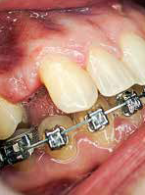

Inwazyjna resorpcja przyszyjkowa zęba 37

Zobacz więcej

lek. stom. Jacek Bilbin